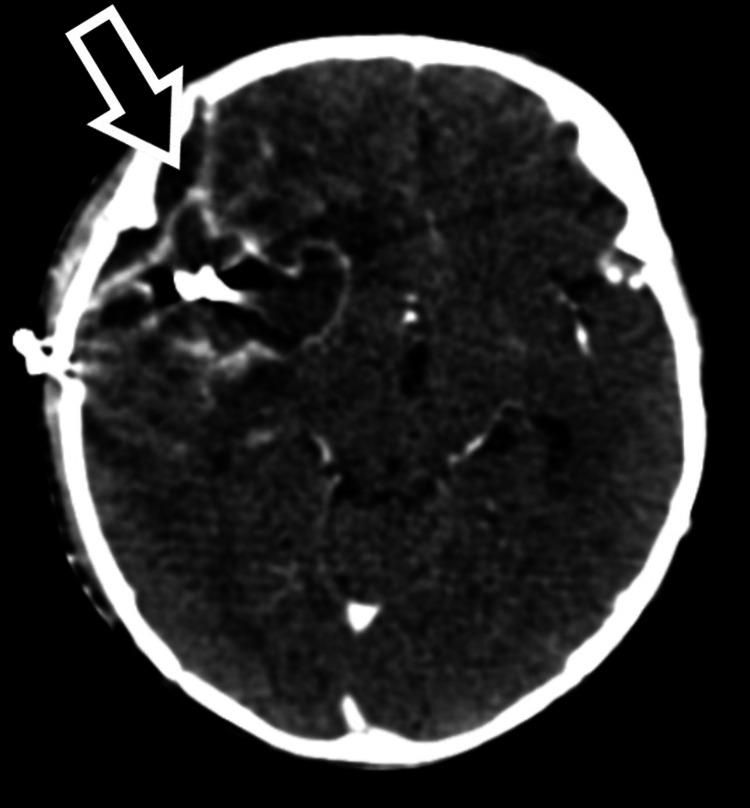

Intracranial aneurysms in pediatric populations are rare, with a distinct clinical profile compared to adult cases. This case report describes the clinical presentation, diagnosis, and treatment of a nine-month-old male with an intracranial aneurysm. The child presented with convulsions, a depressed sensorium, and subsequent neurological deficits. Initial imaging revealed subarachnoid hemorrhage, and further angiographic studies identified an aneurysm rupture from the parietal branch of the right middle cerebral artery. The patient underwent successful neurosurgical intervention, including right craniotomy and aneurysm clipping. Post-operative recovery was marked by gradual neurological improvement and the absence of further seizures. This case underscores the importance of prompt diagnostic imaging and surgical management in pediatric intracranial aneurysms, contributing to favorable outcomes despite the rarity of the condition in this age group.

小儿颅内动脉瘤较为罕见,与成人病例相比具有独特的临床特征。本病例报告描述了一名9个月大患有颅内动脉瘤男性患儿的临床表现、诊断及治疗过程。该患儿出现惊厥、意识不清,随后出现神经功能缺损。初始影像学检查显示蛛网膜下腔出血,进一步血管造影研究确定为右大脑中动脉顶叶分支的动脉瘤破裂。患者接受了成功的神经外科手术干预,包括右开颅手术和动脉瘤夹闭术。术后恢复表现为神经功能逐渐改善且未再发生惊厥。本病例强调了小儿颅内动脉瘤及时进行诊断性影像学检查和手术治疗的重要性,尽管该疾病在这个年龄组中罕见,但仍有助于取得良好预后。